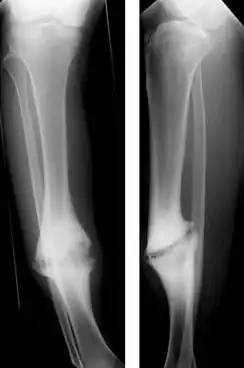

Pseudoartrose (grego antigo para falsa articulação) é uma séria complicação de uma fratura óssea na qual o osso nunca se regenera. Uma cicatriz de tecido fibroso se forma no meio do osso. Sem tratamento resulta em deformidade e prejuízo permanente da função, como por exemplo uma perna torta e incapaz de suportar peso se a pseudoartrose é no fêmur ou na tíbia. O tratamento é cirúrgico e a recuperação demora muitos meses.

- Pseudoartrose hipertrófica: o osso formou um calo ósseo, mas continua fragmentado. Pode ser causado por redução, imobilização ou fixação inadequados. Também pode ser por falta de repouso e fazer muito esforço com o membro lesionado.

Embora não seja tão conhecida da população, é um problema bastante comum e alvo de inúmeros estudos na área científica, entre eles, por exemplo, a deficiência femoral proximal, que é dividida em vários tipos. No Tipo A de deficiência femoral proximal, segundo a classificação de Aitken, verificou-se que o osso se encontra acentuadamente angulado, podendo haver uma pseudoartrose. No Tipo B da classificação de Boyd (tíbia - displásica), ocorre com um encurvamento anterior. A fratura ocorre espontaneamente ou após um trauma mínimo antes dos dois anos de idade. As extremidades ósseas no foco da pseudoartrose são atróficas, lembrando uma ampulheta. Podem estar associadas a manchas café-com-leite, parecidas com as de uma neurofibromatose. Em geral, a fíbula também está comprometida. Este tipo é o mais comum e também o de prognóstico menos favorável que em outros tipos de deformidade congênita, entre os quais se encontra o pé torto, este com bom prognóstico.

O diagnóstico geralmente é feito nas consultas de seguimento seis a oito semanas depois da fratura com raio X e exame físico. Dor, fragilidade e incapacidade funcional indicam que o osso não se consolidou bem.[2] Em caso de dúvida a consolidação inadequada é melhor vista com tomografia computadorizada ou com radiografia dos movimentos disfuncionais (stress Rx).